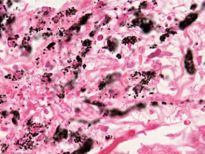

Sivrisinek: Sıtma ve Batı Nil Virüsü